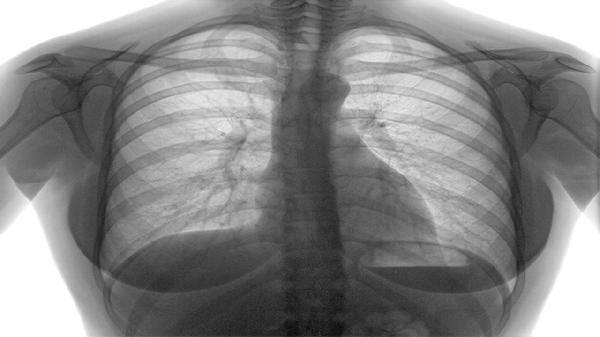

部分晚期患者用药后可能改善恶病质状态及睡眠质量。常见于肺癌骨转移引起的消瘦、失眠等症状。可配合阿法骨化醇软胶囊、唑吡坦片等药物,同时加强营养支持。